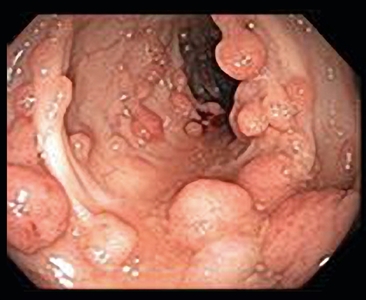

By 1900, several reports had demonstrated that patients with a large number of polyps (later subclassified as adenomas) were at very high risk of CRC and that the pattern of transmission in families was autosomal dominant. In the 20th century, the adenoma-to-carcinoma progression was confirmed, and FAP was recognized as the prototypical model for this progression.[11] Classic FAP is characterized by numerous (hundreds to thousands) adenomatous polyps in the colon and rectum developing after the first decade of life (refer to Figure 3).

Figure 3. Familial adenomatous polyposis is characterized by multiple (>100) adenomatous polyps in the colon and rectum developing after the first decade of life.